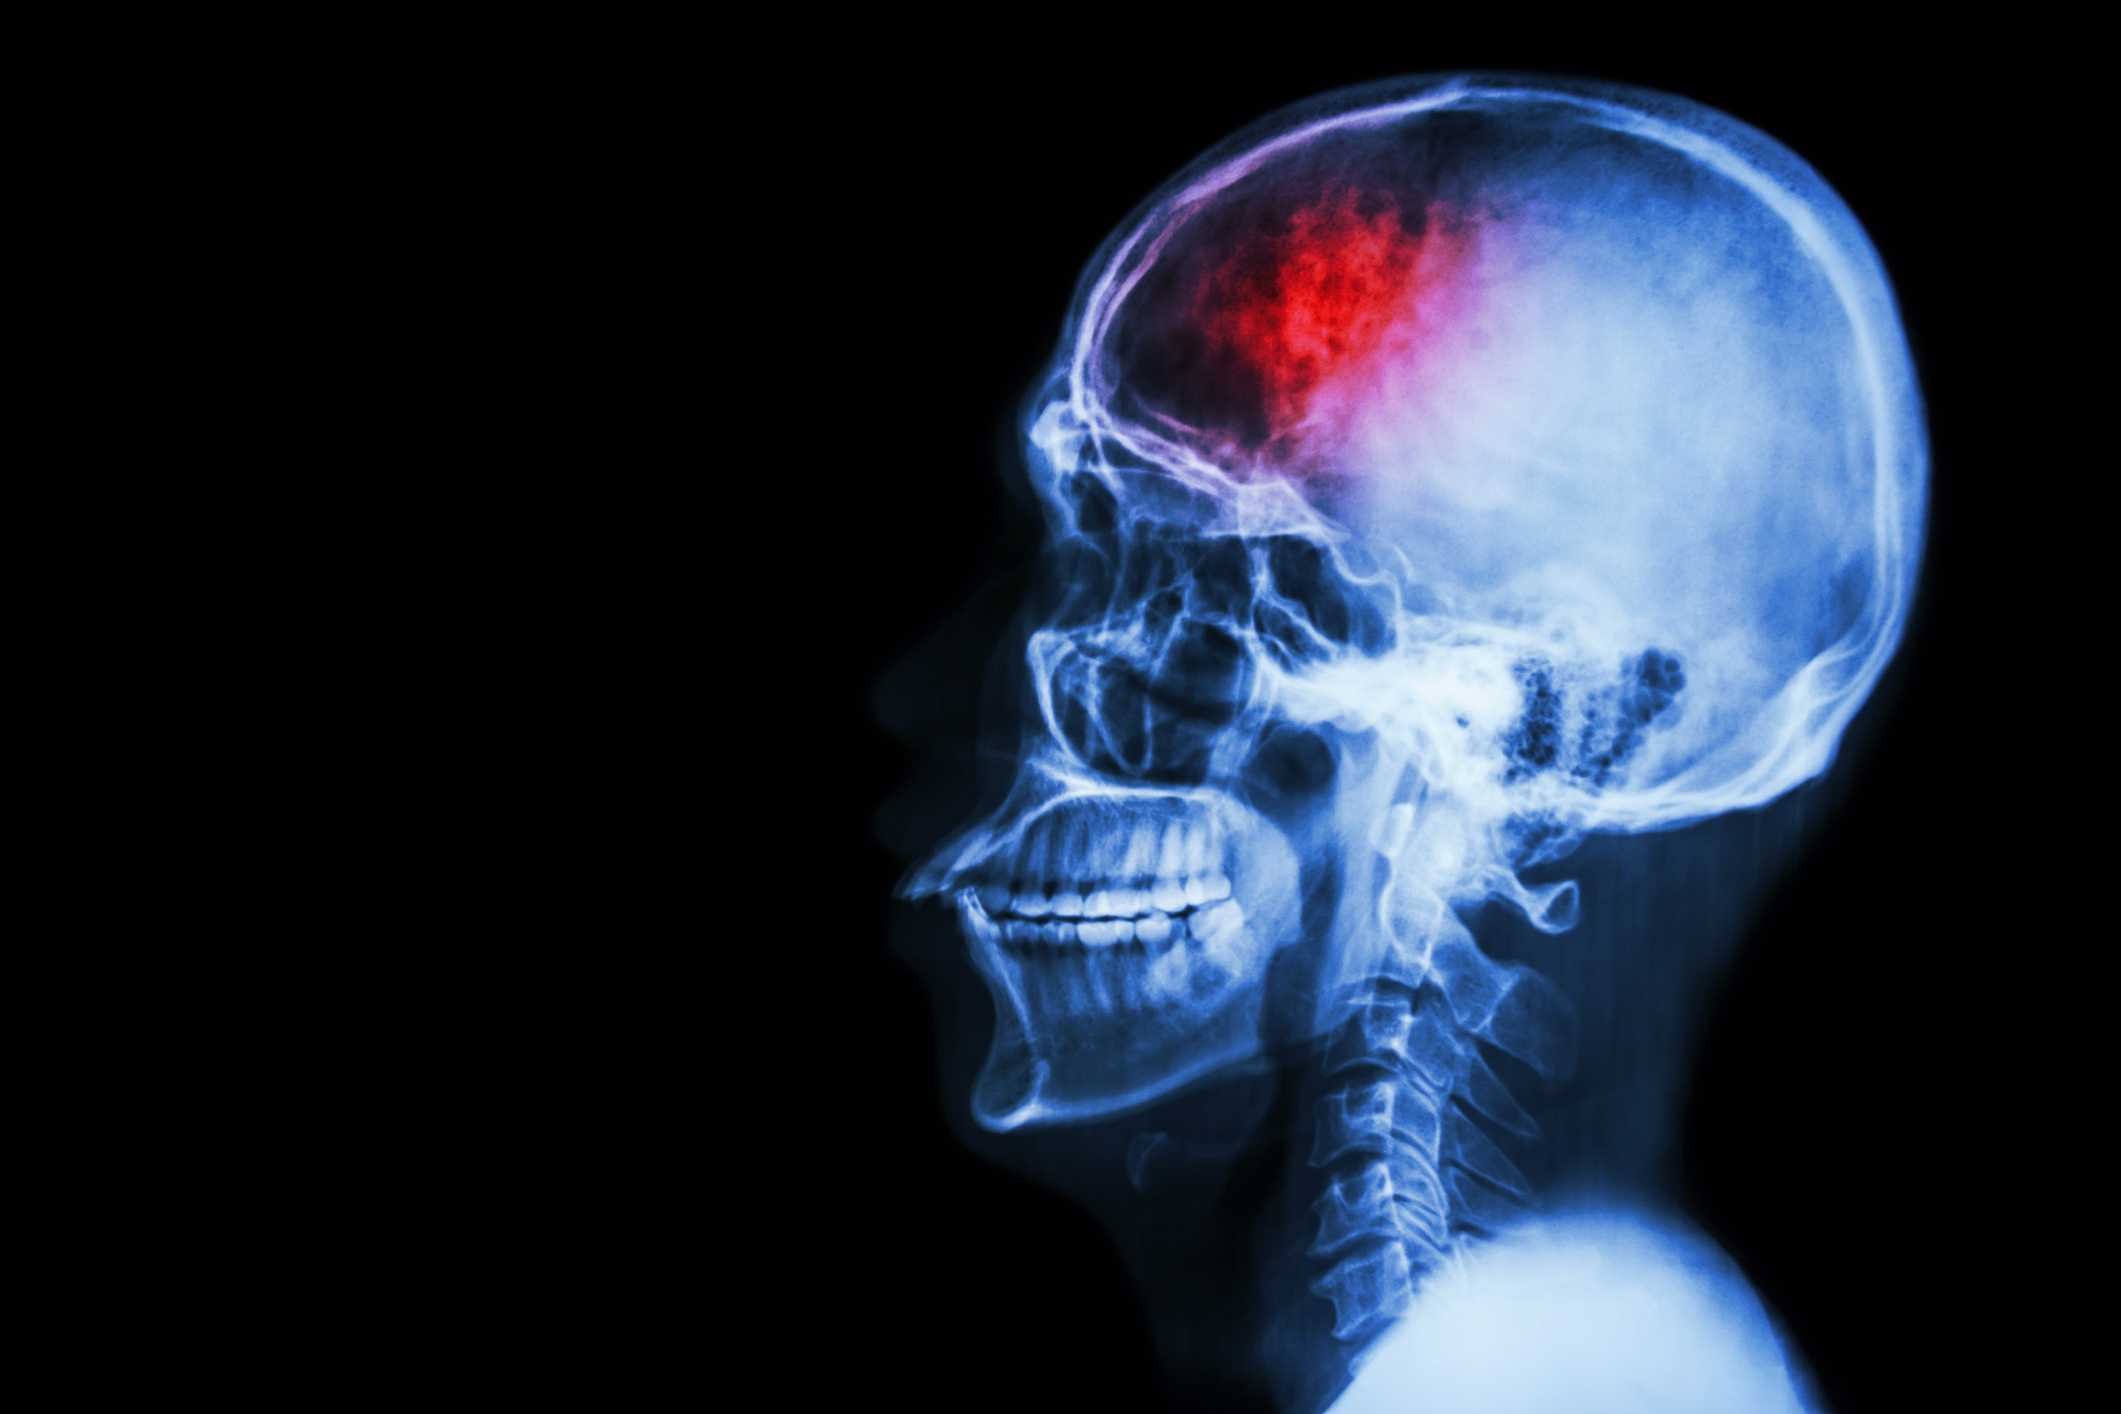

Uncontrolled diabetes can lead to a number of short and long-term health complications, including hypoglycemia, heart disease, nerve damage and amputation, and vision problems.

The majority of these diabetes-related conditions occur as a result of uncontrolled blood glucose levels, particularly elevated blood sugar over a prolonged period of time.

It is essential that diabetics are aware of the complications that can occur as a result of diabetes to ensure that the first symptoms of any possible illness are spotted before they develop.